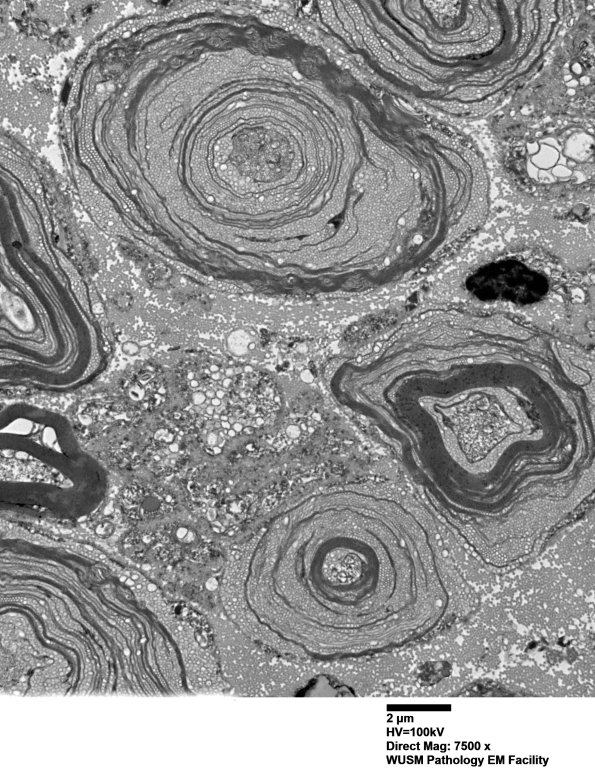

20E3 (Case 20)  Sciatic_015 - Copy

Higher magnification showing global degradation. (electron micrograph)